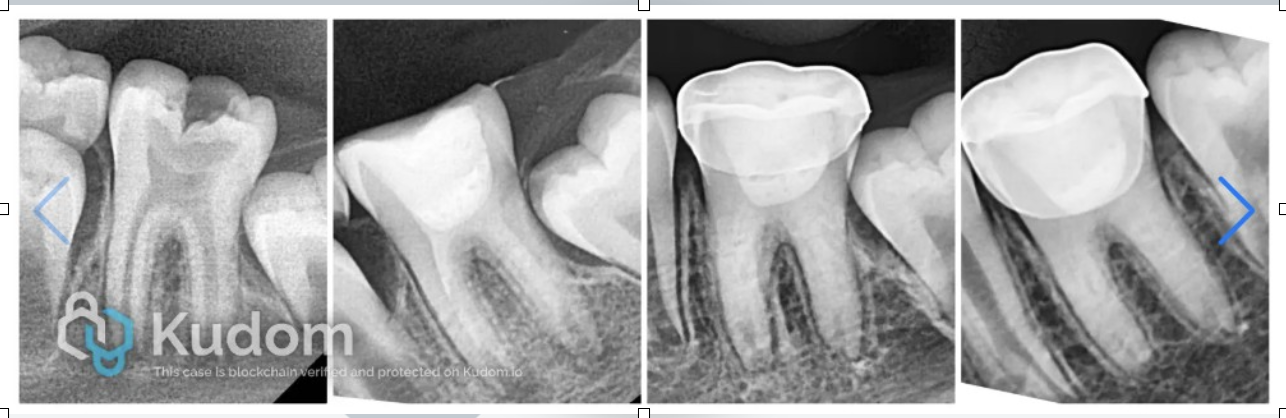

IOPA after cementation of stainless steel crown

Follow-up IOPA at 6 months

Follow-up IOPA at 12 months

Follow-up IOPA at 18 months

Follow-up IOPA at 24 months

Follow-up radiograph at 30 months showed resolution of periapical lesion, and completion of root formation and establishment of lamina dura.